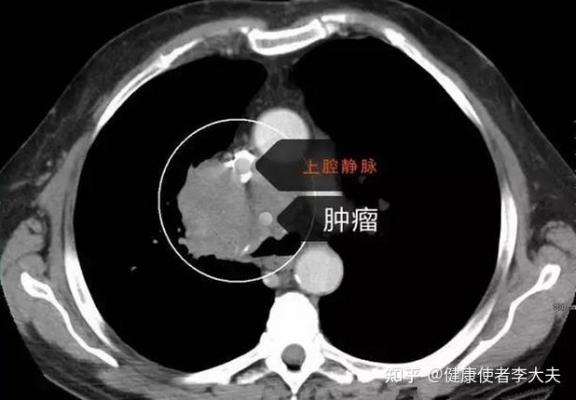

當胰腺出現(xiàn)問題,如胰腺炎或胰腺癌,它會對我們的健康造成重大影響。胰腺炎常常因消化酶異常激活而引起,導致胰腺組織自身消化,而胰腺癌則因其隱匿性和高死亡率,被公認為消化系統(tǒng)中最致命的疾病之一。